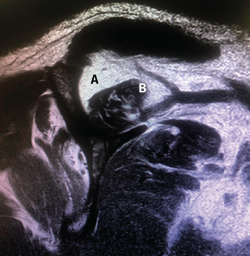

Figura 9. Imagen de resonancia magnética que refleja el grado de atrofia grasa del manguito rotador. A: fosa del supraespinoso; B: atrofia muscular y degeneración grasa del supraespinoso.

Es tal la importancia de la atrofia grasa para la reparación del manguito rotador que numerosos autores han buscado distintas maneras de poder valorarla. Zanetti, Gerber y Hodler describieron el “signo de la tangente” en la RM para estudiar la presencia o ausencia de atrofia del supraespinoso(14), y Thomazeau et al. propusieron calcular la ratio de ocupación de la masa muscular del supraespinoso en la RM comparando el volumen total de la fosa del supraespinoso con el volumen del músculo supraespinoso y observando que esta ratio es significativamente menor en los pacientes con roturas de manguito irreparables(15)(Figura 9).